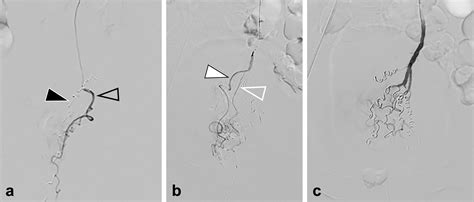

Because it is a minimally invasive technique, it does not require general anesthesia or incisions in the sensitive anal region. Instead, a tiny catheter is guided through a blood vessel in the wrist or groin to the specific arteries supplying the hemorrhoids. Small particles are then injected to block these vessels, successfully reducing the pressure and engorgement of the hemorrhoidal tissues.

2. Guidance: Using real-time X-ray imaging (fluoroscopy), the radiologist navigates a microcatheter through the vascular system.

3. Embolization: Once the specific hemorrhoidal arteries are identified, specialized embolic agents are injected to reduce the blood supply.